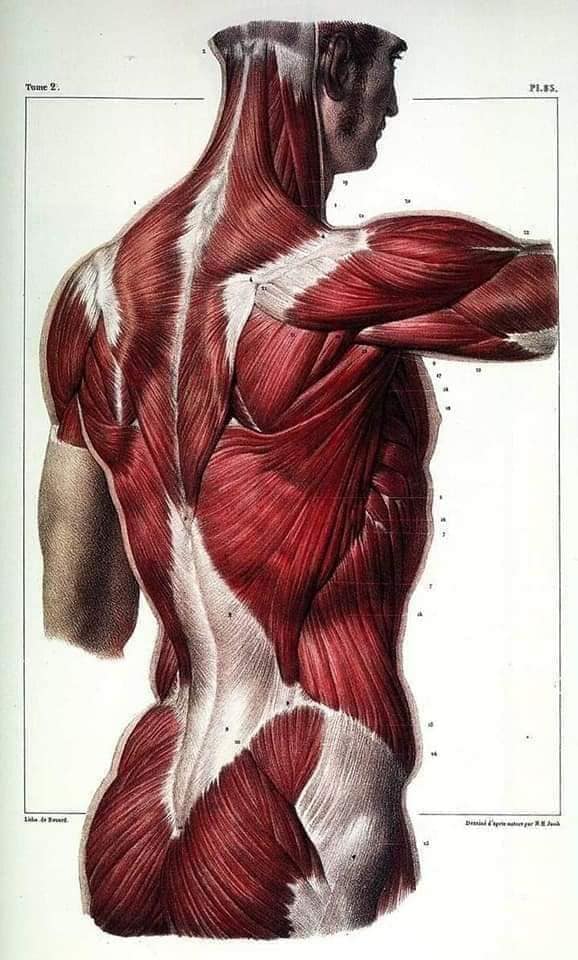

М'язова система людини є однією з основних систем організму, що відповідає за рухи, підтримання пози та стабільність. Вона складається з понад 600 м'язів, які можна класифікувати на скелетні, гладкі та серцеві м'язи. Скелетні м'язи, які є об'єктом нашого детального розгляду, дозволяють контролювати навколишній світ і виконувати різноманітні рухи. Особливу увагу в нашій статті буде приділено шейним і спинним м'язам, оскільки ці групи м'язів мають критичне значення для підтримання правильного постава та функціонування хребта.

Спинні м'язи

Спинні м'язи виконують функції підтримки хребта, а також дозволяють здійснювати рухи тулуба.

Поверхневі спинні м'язи

М'язи, що піднімають лопатку: Трапецієподібний м'яз: великий м'яз, що покриває верхню частину спини. Його функція - підтримка і рух лопаток, а також забезпечення стабільності хребта.

М'язи, що ведуть лопатку до хребта: Широкий м'яз спини: великий м'яз, що розташований в нижній частині спини. Він відповідає за рухи плечей і лопаток, а також за розширення верхньої частини тулуба.

Глибинні спинні м'язи

М'язи, що здійснюють ротацію та нахили

М'язи, що забезпечують ротацію хребта: Ротаційні м'язи: допомагають у здійсненні обертальних рухів тулуба, а також у підтримці рівноваги і стабільності хребта.